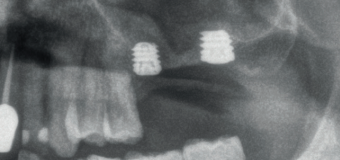

En la Figura 2 se muestran los diámetros y longitudes de los implantes incluidos en el estudio en función de los milímetros de cresta ósea residual en altura. La densitometría media de la zona de inserción del implante del grupo fue de 293,33 HU (+/- 144,99). El torque medio de los implantes estudiados fue de 27,33 Ncm (+/- 16,99). Todos los implantes se cargaron en dos fases quirúrgicas y en todos se llevó a cabo una elevación de seno transcrestal con injerto óseo autólogo particulado obtenido del fresado, embebido en PRGF-Endoret como marterial de injerto. En ninguno de los casos se registraron complicaciones relativas a la cirugía. Los implantes presentaron un seguimiento medio de 13,33 meses tras la carga (+/- 3,09), no encontrándose complicaciones ni fracasos durante este tiempo de seguimiento, por lo que la supervivencia fue del 100%. Todos los implantes fueron rehabilitados mediante prótesis múltiple atornillada mediante elemento intermedio (transepitelial múltiple, Multi-im®), encontrándose dos de los implantes ferulizados a otros de la misma longitud (4,5 mm) y el resto a longitudes mayores. La ratio corona-implante medio para el grupo de estudio fue de 2,43 mm (+/-0,45). La pérdida ósea mesial final media de todos los implantes fue de 0,42 mm (+/- 0,51) y la pérdida ósea distal final media de 0,16 mm (+/-0,34). En las Figuras 3 –13 se muestra uno de los casos incluidos en el estudio.